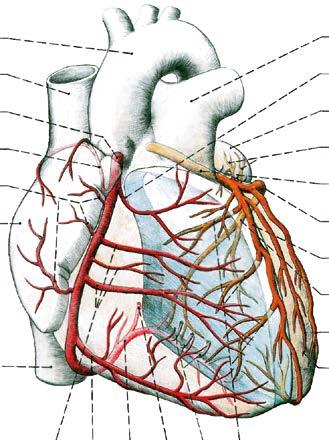

Obr. 8. SRDCE vyjmuté z perikardu; pohled zpředu

1 vena cava superior

2 atrium dextrum

3 auricula dextra

4 ventriculus dexter

5 sulcus coronarius

6 facies sternocostalis

7 vena cava inferior

8 margo acutus

9 auricula sinistra

10 ventriculus sinister

11 margo obtusus

12 sulcus interventricularis anterior

13 aorta ascendens

14 arcus aortae

15 ligamentum arteriosum

16 arteria pulmonalis sinistra

17 truncus pulmonalis

margo acutus je pravý okraj srdce ve formě ostré hrany mezi facies sternocostalis a facies diaphragmatica (obr. 8);

margo obtusus je zaoblený levý okraj, v němž facies sternocostalis plynule přechází ve facies pulmonalis (obr. 9).

Na povrchu srdce, zejména na komorové části, jsou patrná místa průběhu srdeční přepážky –septum interatriale et septum interventriculare –jako povrchové vklesliny:

Obr. 9. SRDCE vyjmuté z perikardu; pohled zezadu; truncus pulmonalis a plicní tepny vedoucí krev zbavenou kyslíku jsou znázorněny modře, stejně jako obě venae cavae

1 auricula sinistra

2 venae pulmonales sinistrae

3 atrium sinistrum

4 margo obtusus

5 ventriculus sinister

6 incisura apicis cordis

7 facies diaphragmatica

8 sulcus interventricularis posterior

9 ventriculus dexter

10 vena cava superior

11 venae pulmonales dextrae

12 atrium dextrum

13 sulcus terminalis

14 prostřižený přechod perikardu v epikard jdoucí kolem velkých žil (porta venarum)

15 vena cava inferior

16 truncus pulmonalis

17 arteria pulmonalis sinistra

18 arcus aortae

19 ligamentum arteriosum

20 arteria pulmonalis dextra

21 aorta ascendens

sulcus interventricularis anterior (obr. 8) – na facies sternocostalis (od sulcus coronarius do blízkosti hrotu srdečního),

sulcus interventricularis posterior (obr. 9) – na facies diaphragmatica (obdobně);